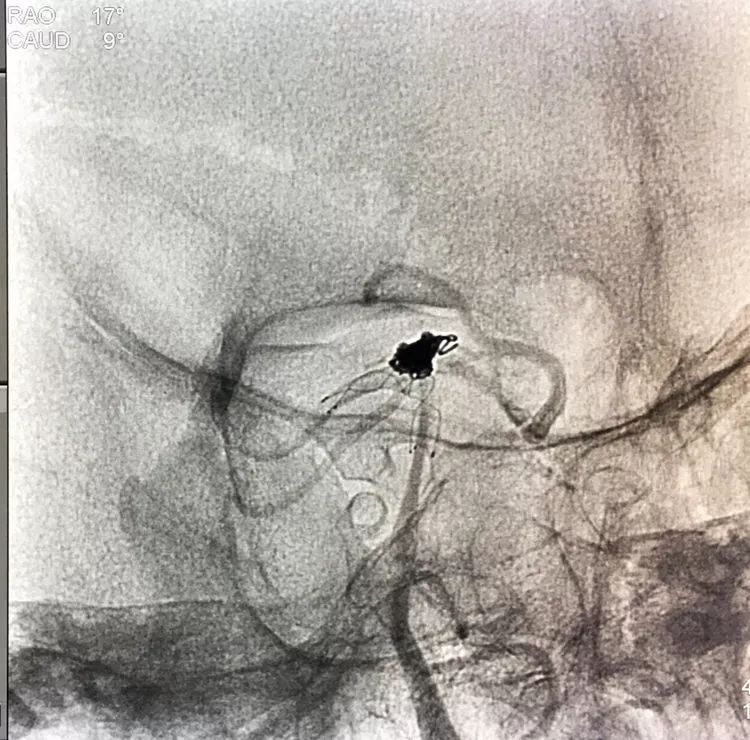

左椎动脉工作位路图

Sychro14微导丝携Headway21支架导管经左椎动脉-基底动脉进入右侧PCA,因瘤颈主要累及右侧PCA,故计划支架跨基底动脉顶端动脉瘤释放于右侧PCA-基底动脉内。

将LVIS支架(3.5×15)跨瘤颈释放于右侧PCA-基底动脉内

在支架保护下输送弹簧圈栓塞瘤腔

此时从工作位(右斜17°反汤9°)看弹簧圈分布致密,微导管头已被顶到瘤颈处

工作位造影看动脉瘤栓塞满意,子瘤已不显影,是不是可以收手了呢?